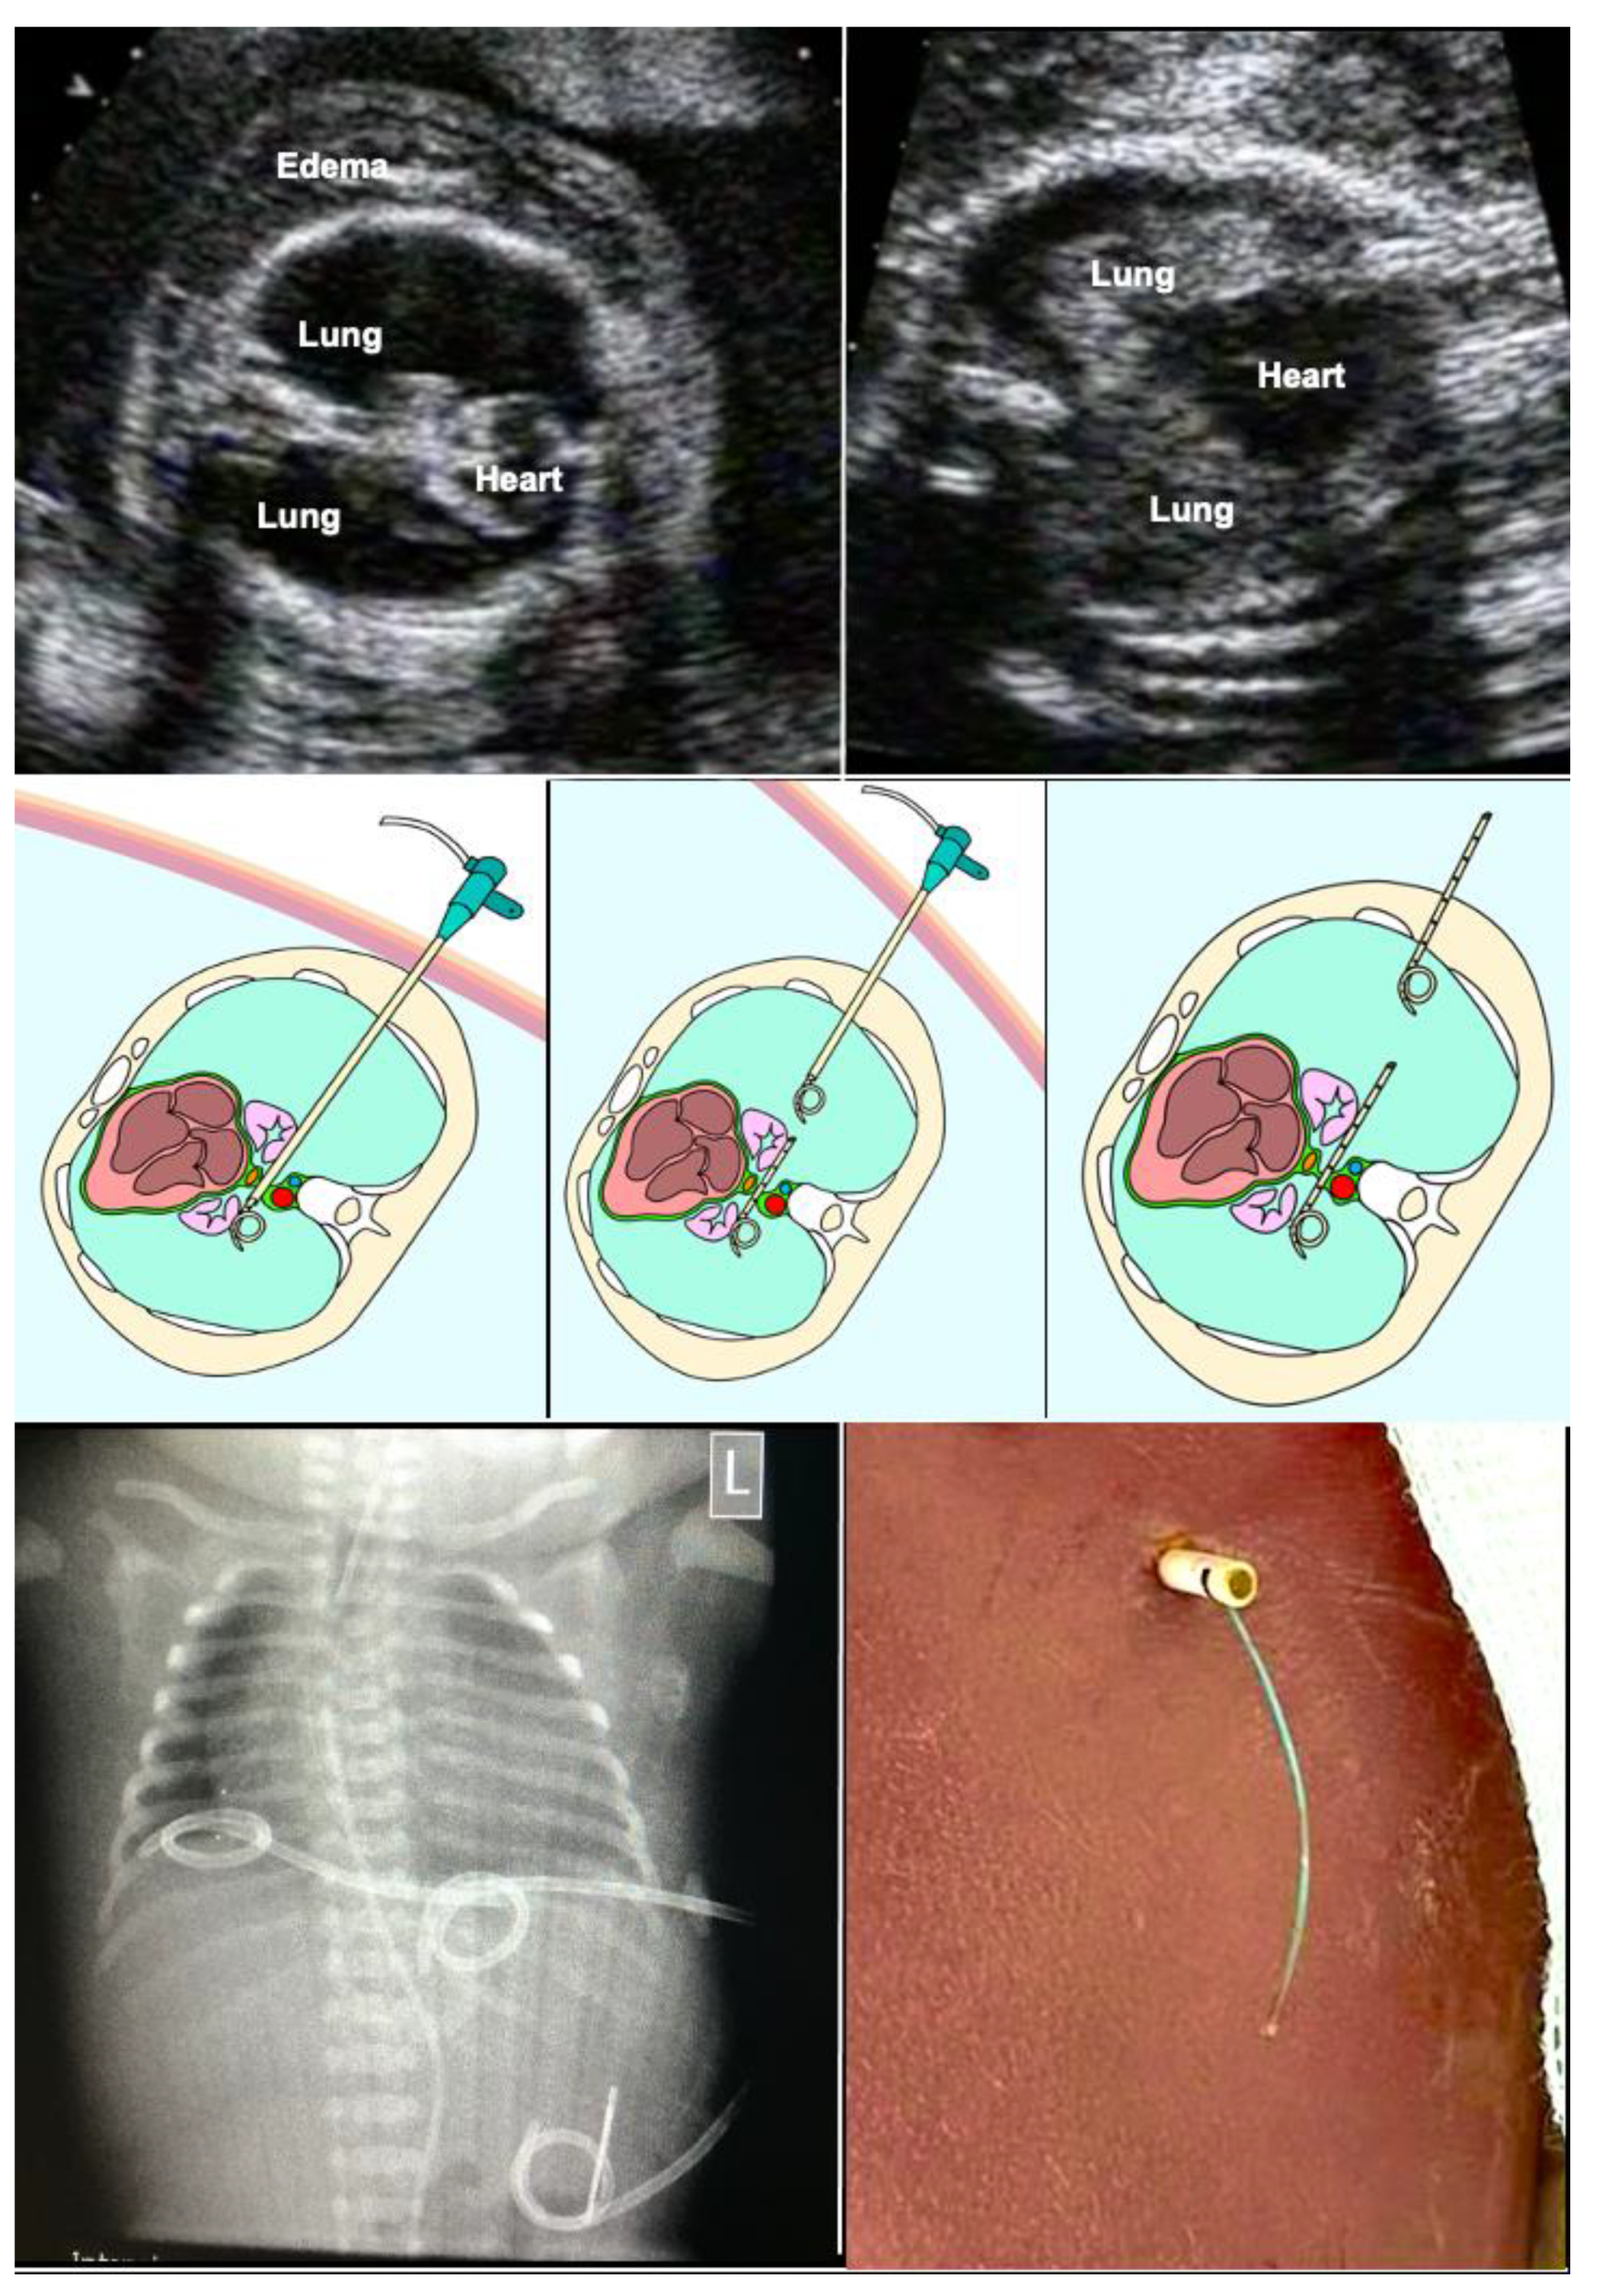

In order to achieve early second trimester shunting as safely as possible, I developed a novel shunt technique for megacystis in 2012. The hallmark of this technique is the use of a single-pigtail catheter that permits vesico-amniotic shunt insertion without any manipulation of fetal position, little strain on the uterine wall and membranes, and no need for amniotic fluid augmentation. The procedure is performed under materno–fetal anesthesia within usually less than five minutes. All of the materials are widely available in hospitals with adult and pediatric intensive care.

In short, following a small maternal skin incision, an 18-gauge needle is advanced into the fetal bladder under ultrasound guidance, preferably via the lower half of the fetal abdomen below the umbilicus (Figure 7). Then, a stiff 0.035′′ guide wire is inserted through the needle shaft, followed by removal of the needle. The wire serves as a rail for the insertion of an 8-F-catheter sheath. This sheath is then used for placing an adequately trimmed single pigtail catheter into the bladder. Then, the catheter sheath is withdrawn without any further manipulation and the incision is closed with a single suture. As soon as the fetus awakens from anesthesia and begins moving again, it pulls the distal catheter end into the amniotic cavity, thereby completing the procedure. Most often, this step does not take longer than a day. Using this literally straightforward approach, amnioinfusion and extensive device manipulations are unnecessary, thus decreasing the risk of the preterm rupture of membranes and enabling early interventions.

Figure 7.

Novel shunt technique for fetuses with megacystis from lower urinary tract obstruction (LUTO) in order to achieve safe, early second trimester shunting. Top left—after a small skin incision, percutaneous ultrasound-guided puncture of the fetal bladder with an 18-gauge needle is performed. Top center—this is followed by insertion of a 0.035′′-guide wire via the needle shaft into the fetal bladder and—top right—insertion of an 8F-sheath—over the wire—into the fetal bladder. Middle left—the tip of the sheath can be seen inside the bladder. Middle center—A single-pigtail catheter has been mounted on the trocar of an 18-gauge needle and is being inserted via the sheath into the fetal bladder. Middle right—after removal of the needle trocar, the pigtail loop becomes visible. Bottom left—after removal of the 8F-sheath, fetal urine drips from the distal end of the catheter. Then, the catheter end is pushed below the skin level of the maternal abdomen and the skin incision is closed with a suture. Bottom right—ultrasound imaging after the procedure demonstrates the pigtail loop within the empty bladder.

This technique was rivaled by the introduction of a far more expensive stent catheter by the company SOMATEX (Berlin, Germany) which also permits more successful and safer early second trimester shunting in fetuses with megacystis [63]. Unfortunately, because of its design (parasols at both ends) and its limited length, dislodgment or trapping can be observed, such that the need for amnioinfusion and repeated placements accompany its use. As an alternative, the Q-shunt that cannot dislodge or be pulled out by the fetus was introduced by Quintero and colleagues [64]. Yet another recent approach that foregoes shunt placement uses a coronary angioplasty catheter via a guide-wire approach for prenatal dilation of posterior urethral valves [65].